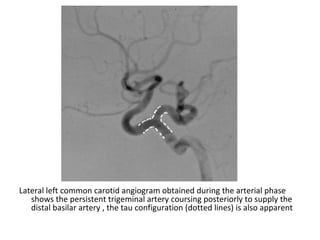

-Persistent Trigeminal Artery :

*The most common persistent carotid-basilar

connection and has an association with

aneurysms

*The persistent trigeminal artery courses

adjacent to the trigeminal nerve , angiography

shows a characteristic trident or tau sign

(resembling the Greek letter τ) on the lateral

view due to the artery’s branching system

*Saltzman type I connects to the basilar artery

while Saltzman type II connects to the

superior cerebellar artery

Lateral left common carotid angiogram obtained during the arterial phase

shows the persistent trigeminal artery coursing posteriorly to supply the

distal basilar artery , the tau configuration (dotted lines) is also apparent